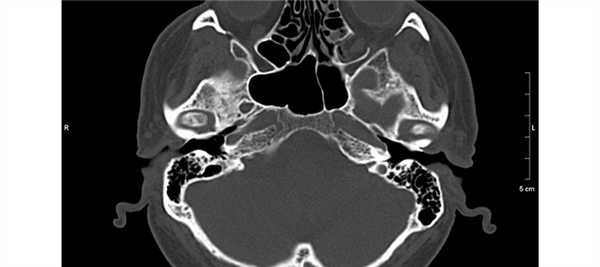

У 5 пациентов 1-й группы отмечалисьпосттравматические изменения височных костей (у 4 процесс носил односторонний характер, у 1 — двусторонний): у пациента с двусторонним поражением височных костей имели место разрыв и дислокация цепи слуховых косточек, изменений в структурах внутреннего уха выявлено не было. У остальных 4 был диагностирован поперечный перелом пирамиды височной кости: линия перелома проходила через область лабиринта и хорошо определялась на томограммах, при этом у одного из этих пациентов была обнаружена полная облитерация улитки, у другого был найден участок костной плотности в преддверии (давность травмы составила 25 и 8 лет соответственно).